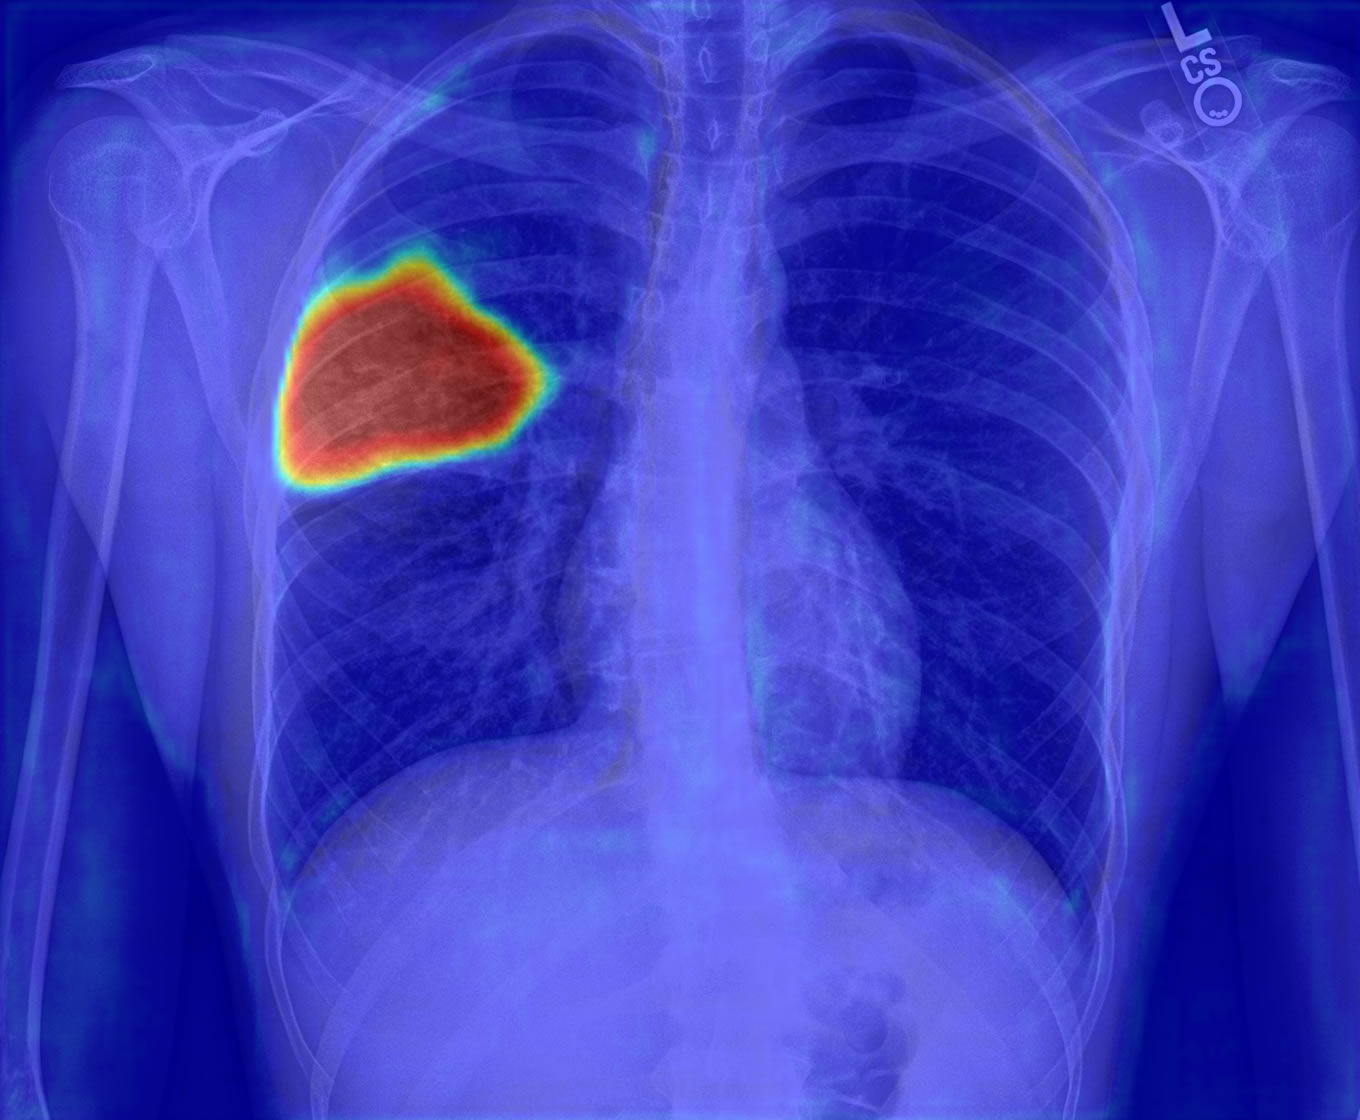

Localización de signos patológicos

Las zonas aéreas de los pulmones son sometidas al análisis de las redes neuronales en búsqueda de anomalíasAnálisis de patrones

DETECCIÓN DE SIGNOS PATOLÓGICOS

| Observaciones | |

| Hallazgos | Consolidación lobar, lóbulo medio del pulmón derecho Reforzamiento de la trama, pulmón derecho |

| Presunción: | 90% infección por neumococos |

| Prioridad asignada: | 72 |

Con el análisis de la imagen y la ubicación de los patrones patológicos se puede realizar las impresiones del estudio de forma automática e instantánea, además de evaluar criterios de calidad de la imagen, a partir de estos datos, se asigna un nivel de urgencia para el paciente.